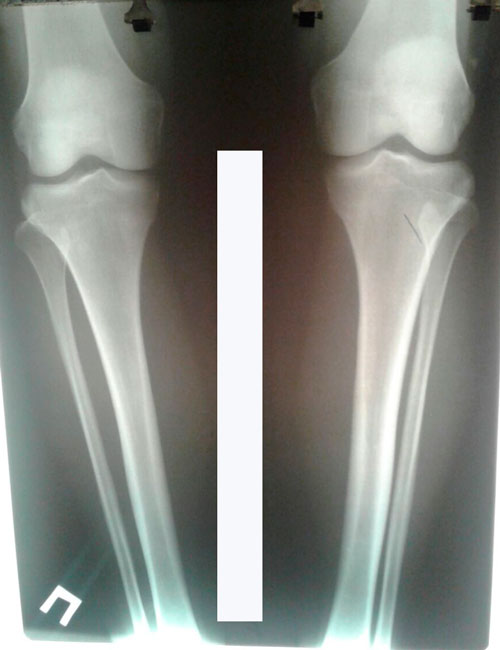

Исходник - 40 лет.

Дата операции - 28.03.2017г.

Дата операции 28.03.2017г.

Дата снятия аппаратов 12.07.2017г.

Срок лечения 109 дней.

Спасибо девочки за красивое фото ножек!